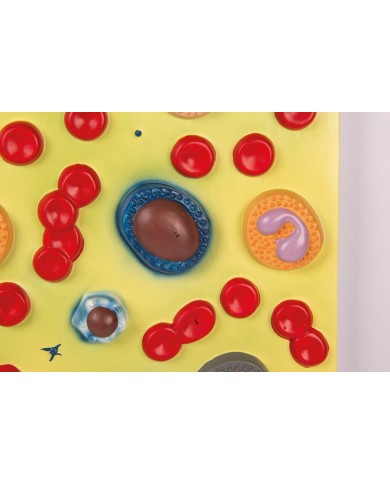

Realizzato in stampa 3D ad elevatissima risoluzione a colori.

Realizzato in stampa 3D ad elevatissima risoluzione a colori.

Realizzato in stampa 3D ad elevatissima risoluzione a colori.